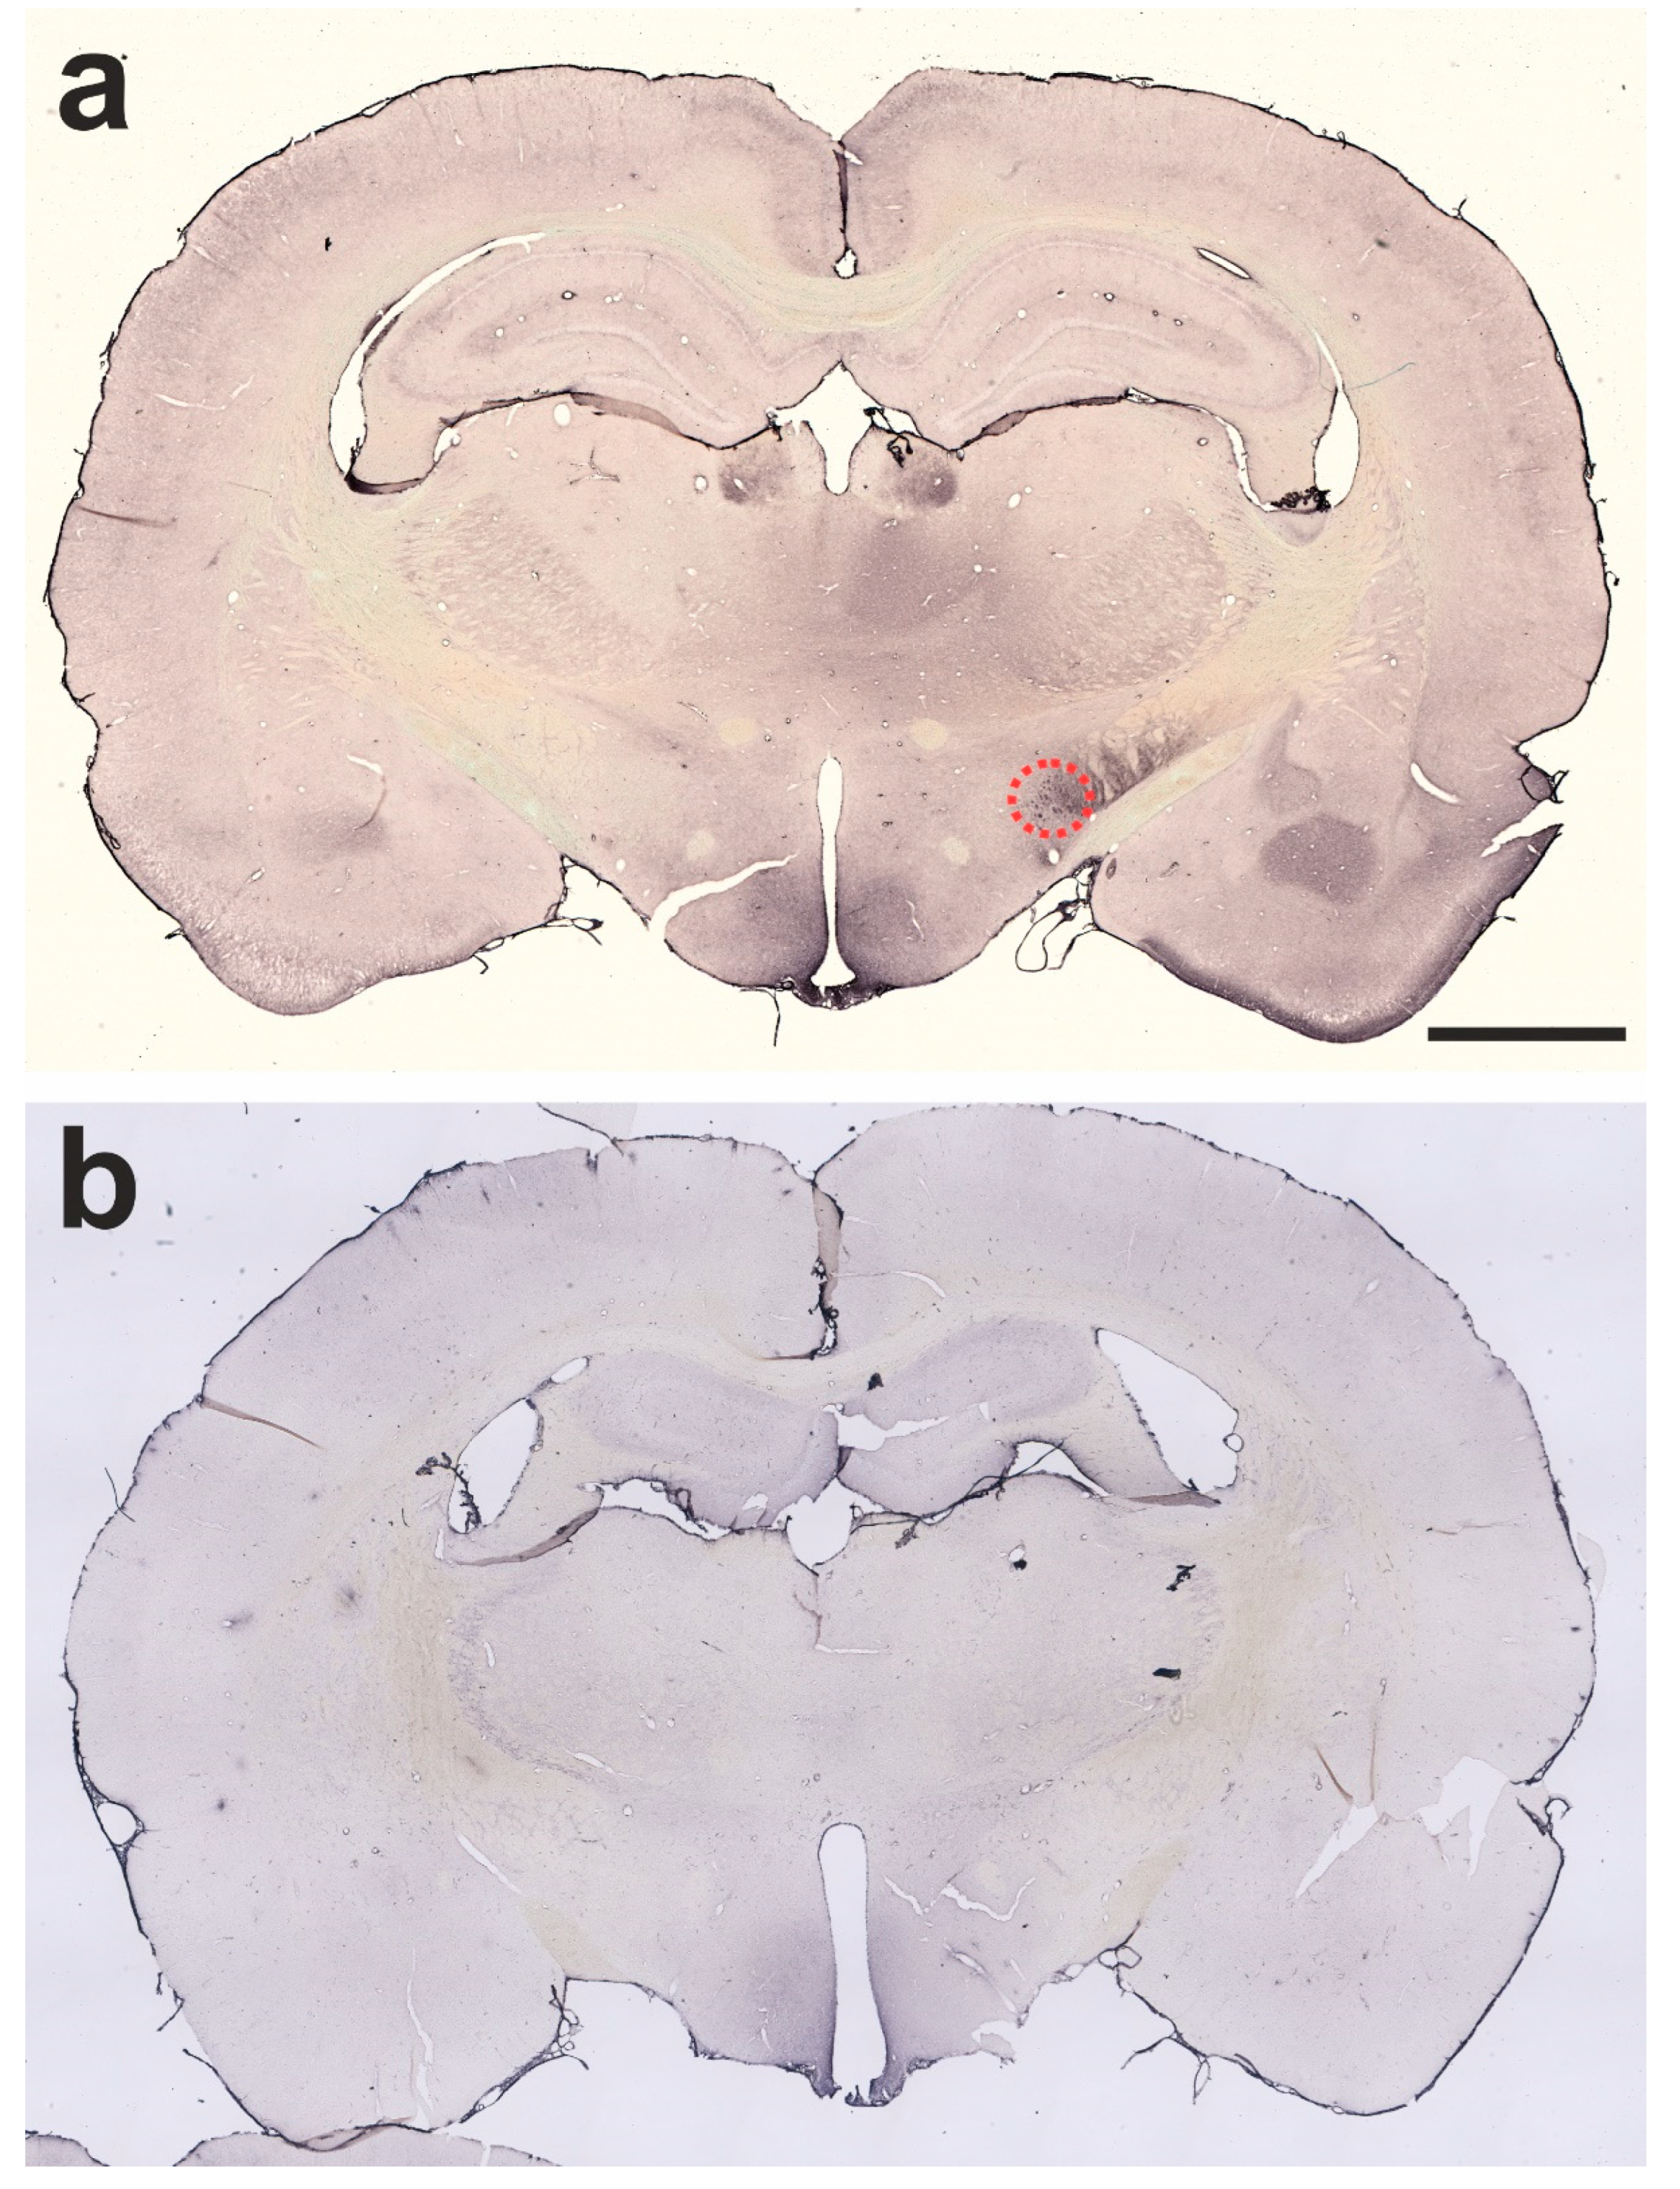

2.1. Verification of Successful BoNT-A Injection—Botulinum Neurotoxin-A-Induced Varicosities

4.2. Stereotactic Injection of BoNT-A into the CPu